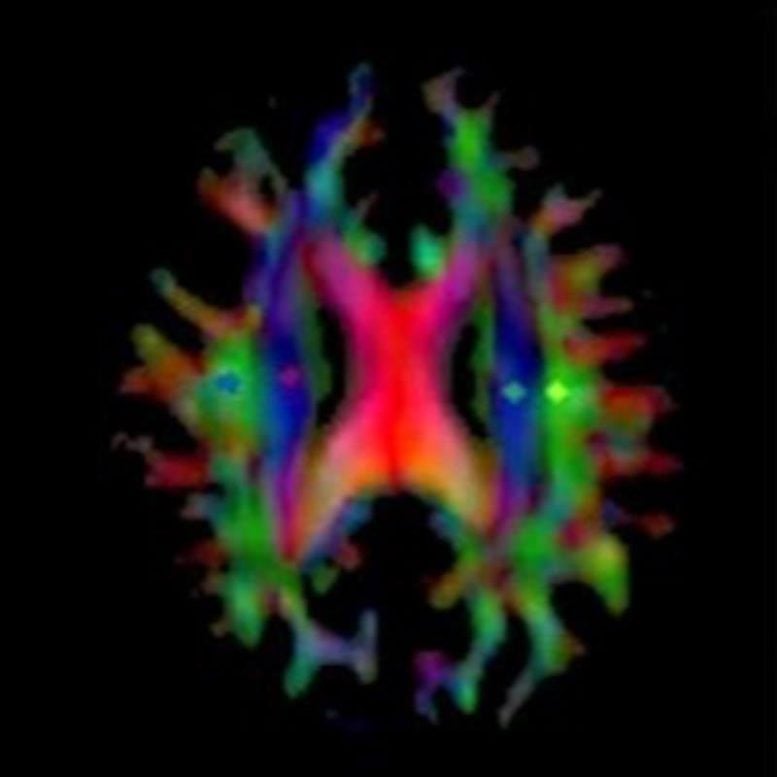

Lecanemab, which was recently approved as a therapeutic option, is intended to lower Aβ levels. To study its effects, the Osaka Metropolitan University team examined the glymphatic system in patients both before and after lecanemab treatment, using the DTI-ALPS index to measure changes.